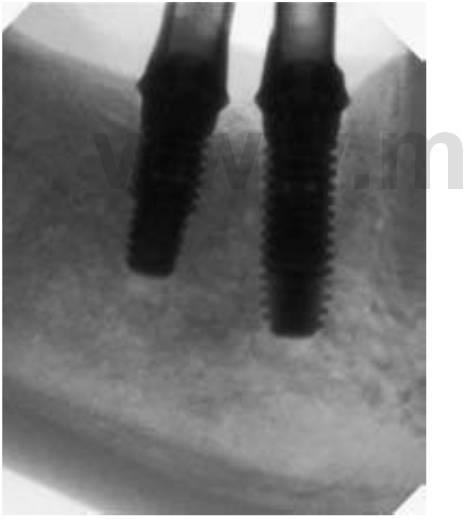

Imágenes intraoperatorias

El empleo de imágenes quirúrgicas ha cambiado dramáticamente la manera en que se completa la cirugía implantológica (cuadros 3-13 y 3-14). En el pasado las desventajas de las radiografías periapicales perioperatorias han condicionado un tiempo de inefíciencia. Para verificar el posicionamiento y localización de un sitio de osteotomía o para la identificación de una estructura vital, el procesamiento de una película de radiografía estándar puede llevar hasta 6 minutos. A causa de ello, los practicantes verificaban raramente el posicionamiento de las estructuras anatómicas durante la cirugía. Con la nueva tecnología radiográfica digital se consiguen imágenes instantáneas, permitiendo completar múltiples imágenes en una fracción de tiempo. Las ventajas adicionales de las imágenes digitales intraoperatorias incluyen la manipulación de las imágenes, su calibración, mediciones exactas y el posicionamiento, y el mantenimiento de un protocolo aséptico (figs. 3-22 y 3-23).